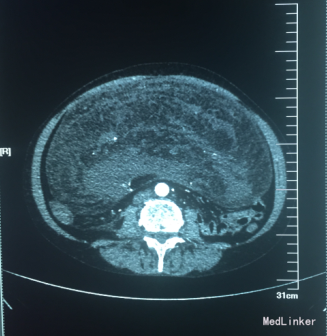

腹部触诊可触及巨大包块,大小约21*17cm,质地韧,活动度差。全腹部+盆腔CT示:,腹腔内巨大软组织肿块,呈混杂密度,内含脂肪及增强血管影,腹部肠管,右肾及周围组织明显受压移位,考虑脂肪肉瘤可能;右侧附件区畸胎瘤;肝脏及双肾可见小圆形低密度灶,边缘光滑,考虑肝多发囊肿,右肾囊肿;盆腔少量积液。

术中将腹壁切开,探查可见肿瘤大小约33*30*15cm,质地韧,不均匀,肿块基地部较大与空肠起始部相连,与周围肠管轻度粘连,空肠起始部系膜表面可见脂肪样包块突起,直径约3-5cm,基底部较宽,与肠系膜相连;余肠系膜再见包块,右下腹可见一直径约10cm略呈球形包块,质地韧包膜完整,仅仅可见一蒂与肠系膜相连。术后病理诊断为:“腹腔”多发性高分化脂肪肉瘤(脂肪瘤样型),部分区混合粘液性脂肪肉瘤,(约占10%)伴局部脂肪坏死及钙化。